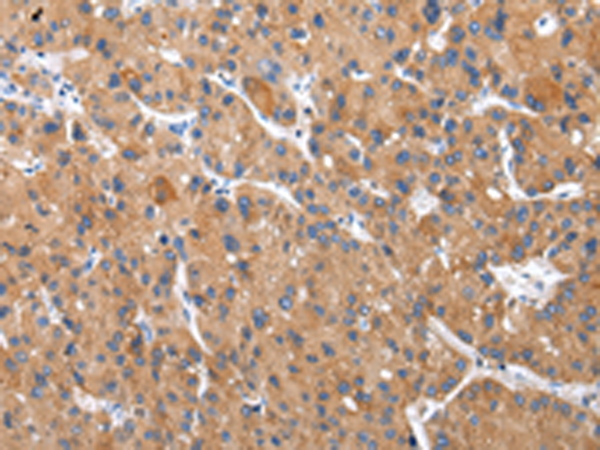

分类: 科研抗体货号: P12417别名: CGA应用: WB,IHC反应种属: Human, Mouse, Rat